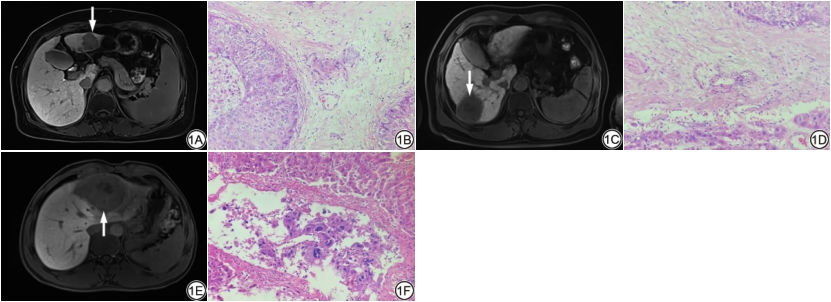

本研究纳入HCC患者病例共370例,其中男295例(79.73%),女75例(20.27%),年龄(57.73±9.80)岁。根据组织病理学结果,将患者分为M0级(192例)、M1级(132例)和M2级(46例)(图1)。统计结果显示三组患者在年龄、性别、甲胎蛋白(alpha-fetal protein, AFP)水平、是否肝硬化、包膜完整性、多灶性方面差异均无统计学意义(P>0.05)(表1)。

(1A), the corresponding pathological picture (1B) is confirmed M0; 1C, 1D: Female, 63 years old, HCC of the right lobe, Gd-EOB-DTPA enhanced MRI HBP image (1C), the corresponding pathological picture (1D) is confirmed M1; 1E, 1F: Male, 67 years old; HCC of the left lobe, Gd-EOB-DTPA enhanced MRI HBP image (1E), the corresponding pathological picture (1F) is confirmed M2.